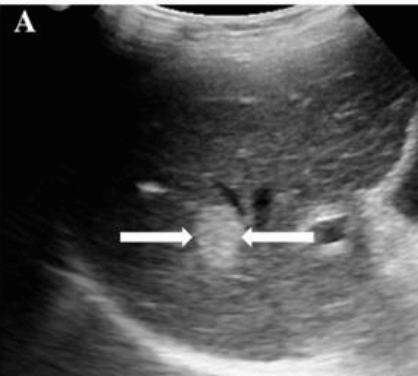

US finding

- 동일한 크기의 다발성 종괴가 나타난다.

- 고에코의 다발성 종괴: 대장암이 많으나 위암도 비교적 흔하다.

- 저에코의 다발성 종괴: 유방암, 폐암등에서 나타난다.

- 석회화나 내부 낭성 변성은 전이성 간종양을 시사하는 소견이다.

- bull's eys sign (종양 변연에 중심부가 고에코이고 경계부가 저에코인 두꺼운 띠가 보인다)

- cluster sign (종양이 융합하여 분엽모양을 이루어 마치 포도송이 모양을 나타낸다)